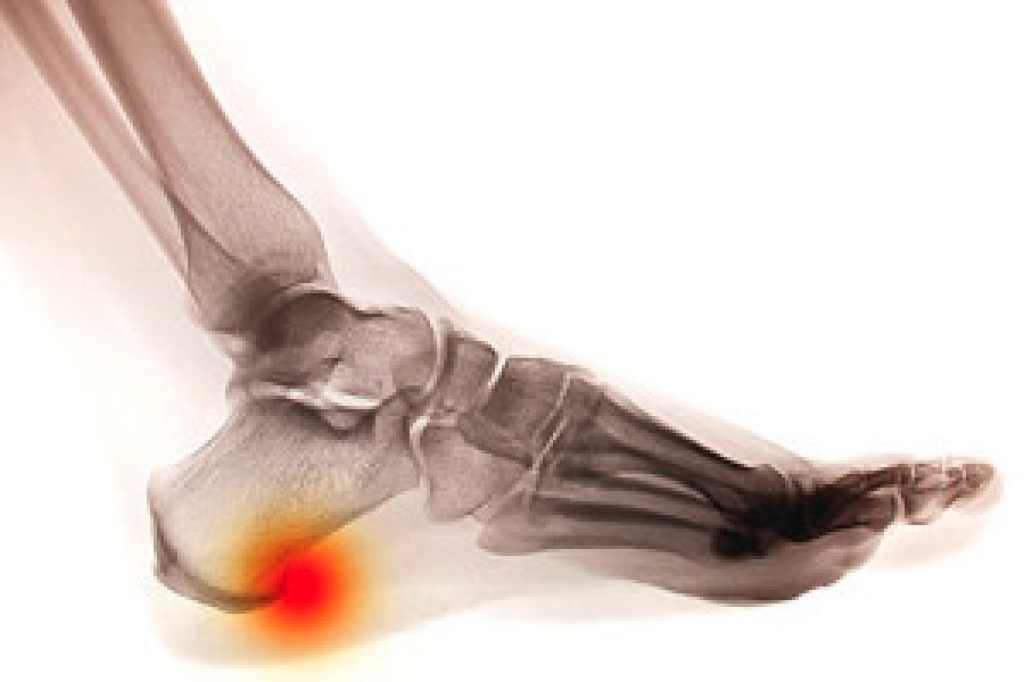

A heel spur is a bony growth that forms on the underside of the heel bone, often causing significant discomfort. This condition typically arises from repetitive stress or strain on the foot, which can lead to inflammation of the plantar fascia, the ligament that supports the arch. Risk factors can include obesity, prolonged standing, improper footwear, and activities that put excessive pressure on the feet. The main symptom is sharp, stabbing pain in the heel, particularly during the first steps in the morning or after periods of rest. To prevent heel spurs, it is essential to wear supportive shoes, maintain a healthy weight, and avoid excessive strain on the feet. Stretching exercises for the Achilles tendon and the plantar fascia can also help reduce the risk of developing this condition. If you have heel pain, it is suggested that you promptly schedule an appointment with a podiatrist who can accurately diagnose and treat heel spurs.

Heel spurs are formed by calcium deposits on the back of the foot where the heel is. This can also be caused by small fragments of bone breaking off one section of the foot, attaching onto the back of the foot. Heel spurs can also be bone growth on the back of the foot and may grow in the direction of the arch of the foot.

The pain associated with spurs is often because of weight placed on the feet. When someone is walking, their entire weight is concentrated on the feet. Bone spurs then have the tendency to affect other bones and tissues around the foot. As the pain continues, the feet will become tender and sensitive over time.